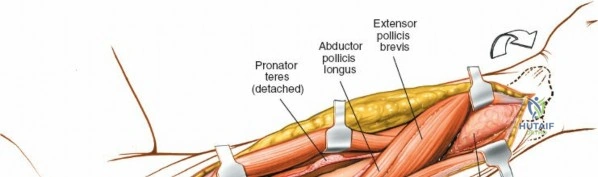

The proximal radius is draped by the supinator muscle. The PIN passes directly through the belly of the supinator. To protect the nerve, the forearm must be fully supinated. Supination dynamically rotates the radius, carrying the insertion of the supinator anteriorly and simultaneously displacing the PIN laterally and posteriorly, safely away from the surgical field.

With the forearm fully supinated, identify the broad insertion of the supinator on the anterior aspect of the radius. Incise the supinator directly along the line of its insertion onto the bone. It is critical to detach the muscle by dividing its insertion sharply at the bone, rather than splitting the muscle belly, which would risk cutting the PIN.

Proceed with strict subperiosteal dissection, elevating the supinator laterally off the bone. This is one of the rare instances in orthopedic surgery where the safety gained by staying in a subperiosteal plane completely outweighs the theoretical vascular damage to the bone caused by periosteal stripping. The elevated supinator muscle belly now acts as a protective cushion for the PIN.

Once the proximal radius is exposed, great care must be taken with retractor placement. Never place Hohmann or levering retractors blindly around the posterior surface of the radial neck. Because the PIN may touch the bone posteriorly in up to 25% of patients, a posteriorly placed retractor can easily crush the nerve against the radial cortex. Instead, use gentle right-angle retractors or place retractors only on the anterior and lateral aspects of the bone, utilizing the elevated supinator as a shield.